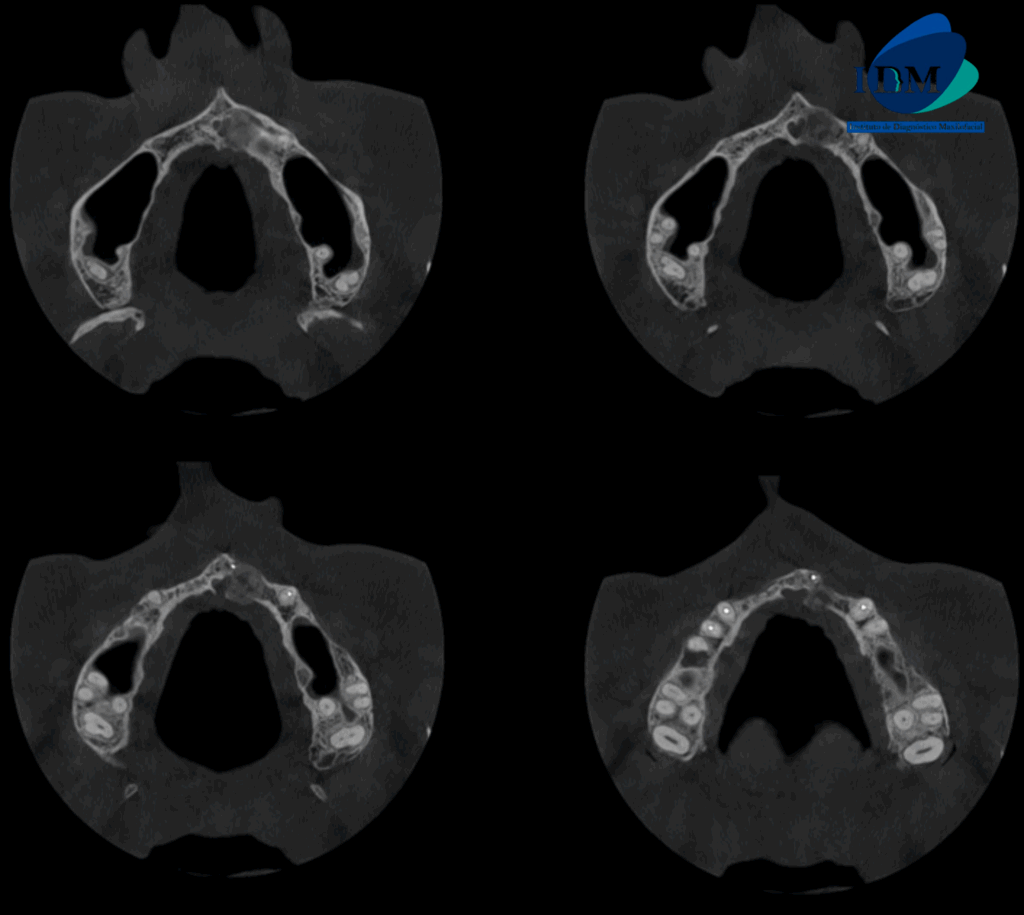

A la evaluación de la tomografía volumétrica (CBCT) en los cortes axiales (Figura 2) y transaxiales (Figura 3), se aprecia imagen mixta localizada a nivel apical de pieza 21, de limites definidos, que se extiende en sentido cefálico caudal desde piso de fosa nasal izquierda hasta apical de pieza 21, en sentido mesio distal desde cortical de conducto nasopalatino hasta nivel de zona de pieza 22, ocasionando adelgazamiento y expansión de tabla ósea vestibular y palatina, adelgazamiento del piso de fosa nasal izquierda, borramiento parcial de cortical de conducto nasopalatino.

CORTES AXIALES